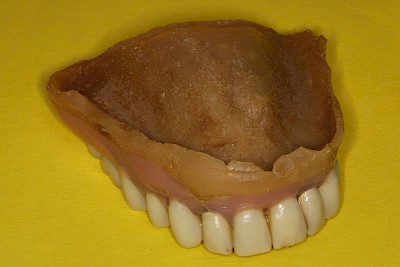

Verfärbung, Abnutzung & Umbau

Verfärbungen, Abnutzungserscheinungen sind eher unkritisch. Sind allerdings Prothesenzähne stark abgenutzt, kann es zunehmend schwerfallen, die Nahrung gut zu zerkleinern. Zudem kann es zu einer Biss-Senkung kommen und in der Folge können die Mundwinkel sich entzünden (Mundwinkelrhagaden).

Weichbleibende Unterfütterung

Weichbleibende Unterfütterungen werden durchgeführt, wenn es immer wieder zu Prothesendruckstellen kommt. Allerdings lassen sich weichbleibende Unterfütterungsmaterialien nicht so gut reinigen. Es kommt schneller zu Belagsbildungen und Pilzbefall. Mit der Zeit können zudem die Materialien verspröden, was die Belagsbildung weiter begünstigt. Dann spätestens ist es sinnvoll und notwendig, den Zahnarzt zu verständigen.